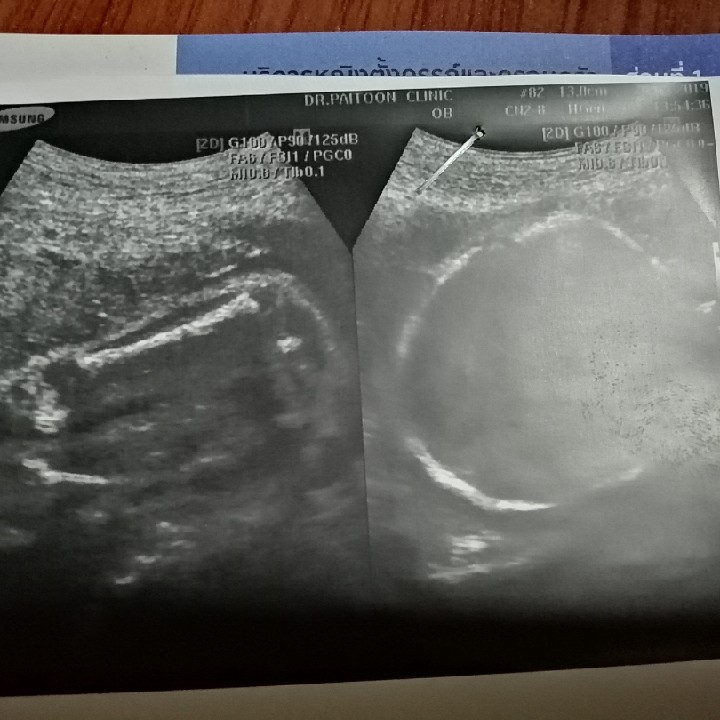

ลูกสาวค่ะ น้องแฝด

ลูกสาวค่าา 👯♀️